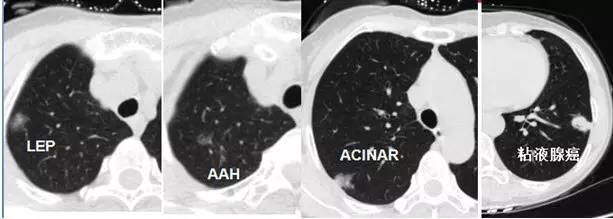

在初期(< 1 cm)往往很纯、密度很低、圆脸、边界也清晰,这时还不一定是恶性的,可以称为「纯 GGO」。切除后多证实为腺瘤样不典型增生(AAH,癌前病变)或原位腺癌(AIS,未侵犯周围血管间质、不会转移,5 年生存率 100%),极端情况下也可是微浸润腺癌(MIA,侵犯周围血管间质 < 5 mm,不会转移,切除后 5 年生存率 100%)。 20% 的纯 GGO 在随访过程中病灶会增大或变成混合型 GGO,而 40% 的混合型 GGO 在随访中会增大或实变区增大。 当逐渐长大进展,纯 GGO 的实性成分增加,成为「混合性GGO」。有时,还会出现分叶、毛刺、空泡,胸膜凹陷,血管密集等改变,这时多数已经是恶性了,为浸润性腺癌——可侵犯血管、肺内或全身转移。 局灶性肺 GGO 的随访

4 个肿瘤一次全切除后,分别为 4 种类型的肺癌